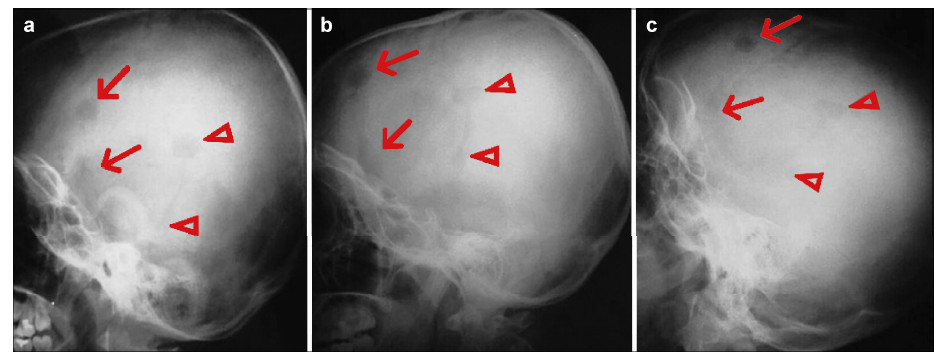

3 Results and discussion For each patient,there were no inflammatory responses, itching,or exudation at the surgical sites,and the wounds healed well. 3.1 Case 1 Figure 4 shows plain radiographs from the patient’s follow‐up. At the sites treated with mineralized collagen burr‐hole plugs (noted by triangles),bone mineral density gradually increased and approximated the host temporal bone. The interfaces between the implants and the host bone became fuzzy,indicating a remarkable osteogenesis effect. However,the bone mineral density of the blank control sites (noted by arrows) remained obviously lower than that of the surrounding normal bone tissue.

| Figure 4 Post‐operative plain radiographs from case 1 (a. 1‐month follow‐up; b. 3‐month follow‐up; c. 10‐month follow‐up). |